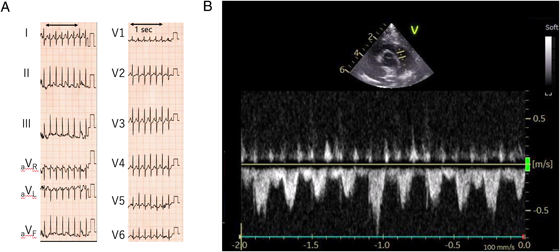

Current medical history: At 4 months of age, the patient re-visited his initial physician for a routine VSD checkup. During echocardiography to evaluate the VSD, his HR accelerated markedly with crying. The HR elevation appeared not to be attributed solely to sinus tachycardia associated with crying. As a precise measurement was challenging, the waveform of blood flow velocity across the main pulmonary artery was assessed using the pulse-wave Doppler method. The circumstance was confirmed with 12-lead ECG (Fig. 1A, B). His HR exceeded 300 beats/minute, prompting transfer to our hospital for further evaluation of the tachyarrhythmia.

Clinical course after hospitalization: As mentioned above, 12-lead ECG performed by the previous physician revealed a marked tachycardia with an HR of 326 beats/minute. Initially, the patient was suspected to have a narrow QRS tachycardia with an unclear P wave and a constant RR interval, leading to a provisional diagnosis of atrioventricular reciprocating tachycardia (AVRT). 12-lead ECG performed upon arrival at our hospital revealed HR of 250 beats/minute, lower than the previously recorded figure. Still, the tachycardia persisted. Similar to the previous findings, the updated 12-lead ECG displayed a narrow QRS tachycardia with a constant RR interval. P wave was clearly observed preceding QRS wave, and there was no delta (Δ) wave (Fig. 3).

HR >200 beats/minute during a tachycardia attack poses a high risk for progression to congestive heart failure.1) Active diagnostic measures, such as 12-lead ECG, prolonged ECG monitoring, Holter ECG, and drug loading, are essential when distinguishing between tachyarrhythmias and sinus tachycardia. Additionally, pulmonary arterial blood flow velocity quantification using Doppler imaging can provide valuable diagnostic insight on echocardiography, as performed in this case.

In this case, a preceding P wave was observed during the tachycardia at a heart rate of 250 beats/minute, and Δ wave became apparent after ATP administration. It is likely because conduction through an accessory pathway was unmasked due to suppression of normal atrioventricular conduction. Additionally, high-dose ATP suppressed fast P wave (HR >250 beats/minute) and slower P wave (HR around 90 beats/minute) emerged, suggesting that the ATP-sensitive AT was temporarily suppressed. This allowed a transient return to sinus rhythm with a WPW syndrome pattern.